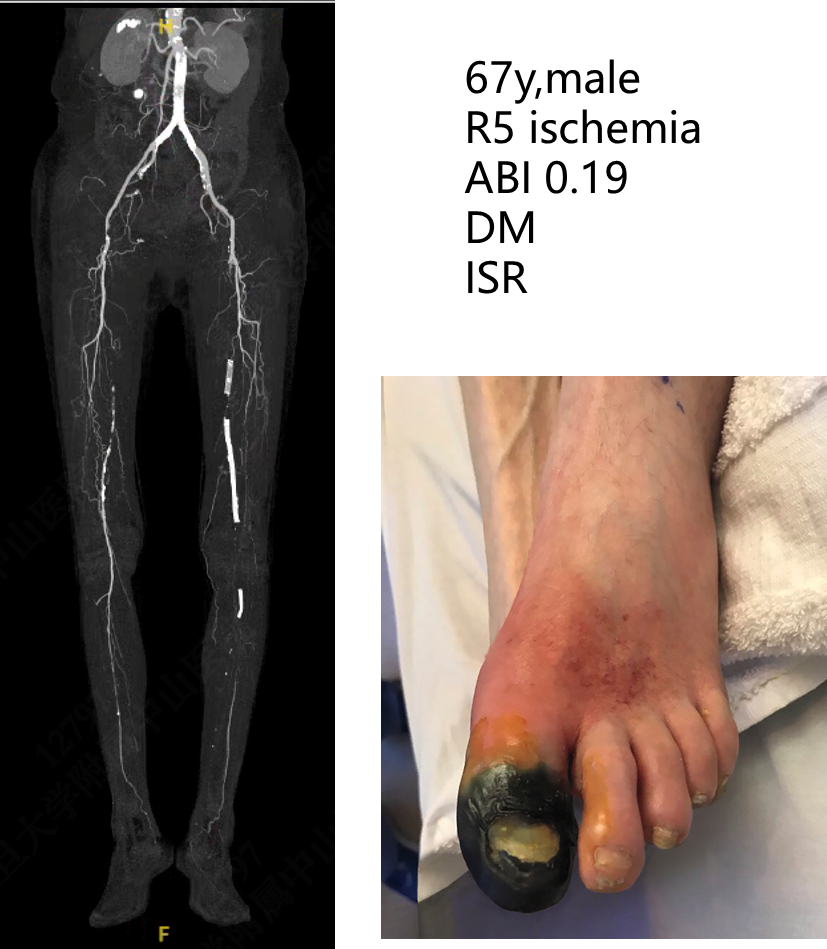

★ Case 2

4次EVTs反复复发:R5 ischemia → 腘P3-足背non-reversed GSV旁路

在GSV条件良好,且手术风险可控的患者→Bypass

在高手术风险的CLTI患者→Endo

在没有GSV可用,且手术风险仍较低的患者→两者均可

高比例R5/6、WIfI III/IV、GLASS III

腔内失效病例:63%